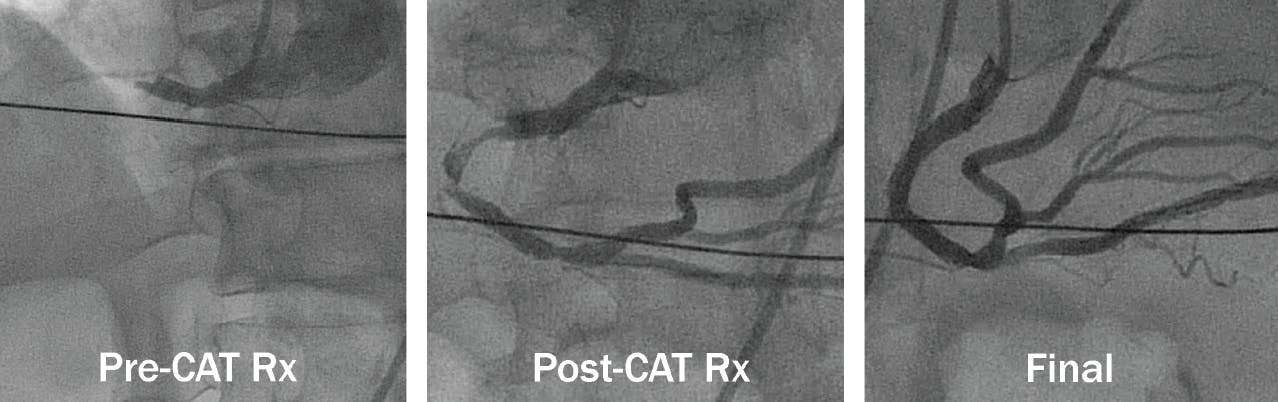

The CAT Rx device is compatible with all coronary arteries. Figure 3 shows an example case of a patient presenting with ventricular fibrillation arrest with right coronary artery STEMI. Results are shown pre-CAT Rx, post-CAT Rx, and final angiography with normalized myocardial blush. It is worth noting that up-front CAT Rx use revealed the culprit spontaneous dissection, facilitating direct stenting of the lesion without extending beyond the target area.

Figure 3. Right coronary artery STEMI utilizing CAT Rx.